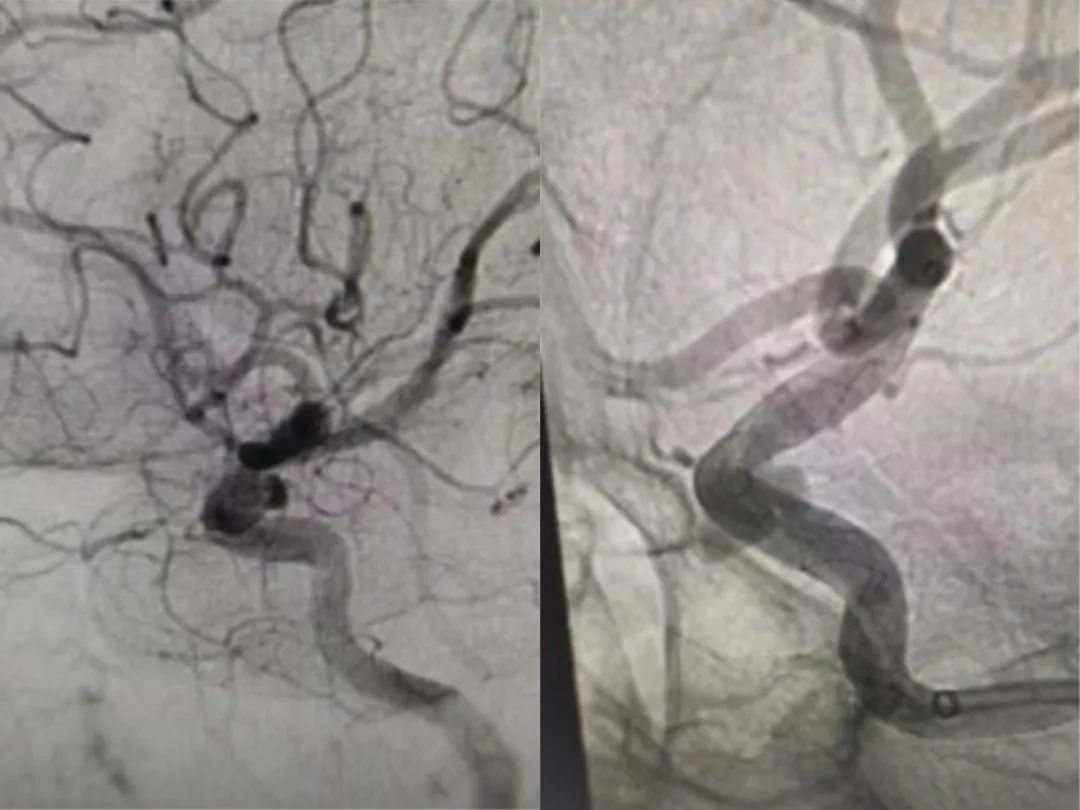

传统开颅手术面临创伤大、风险高等问题,而普通介入治疗又难以稳定封堵不规则瘤体,且在操作中易破裂。经过详细的研究,肖主任团队最终决定采用一种最新技术——血流导向密网支架植入术,为黄阿姨拆除颅内的“隐形炸弹”。当天,在局部麻醉下,肖主任和朱胜华副主任医师通过全脑血管造影、高分辨率MRI及三维重建技术,明确动脉瘤位置、形态及与周围血管、神经的毗邻关系,施行血流导向密网支架植入术,整个过程耗时不到30分钟。术后造影显示支架完美贴壁,载瘤动脉重塑良好,分支血管零损伤。手术6小时后即恢复自主活动,三天后康复出院。